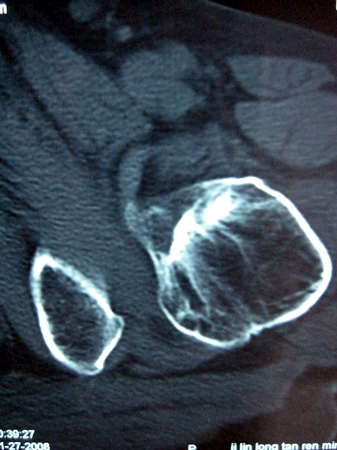

以下是引用lkc8963在2008-12-19 21:19:00的发言:[br]左?右?患侧大转子上移,股骨颈骨质浓杂,髋周见多发条片状骨化影,以小转子为著,多为陈旧性股骨颈骨折后改变并骨化性肌炎.请咨询既往史!